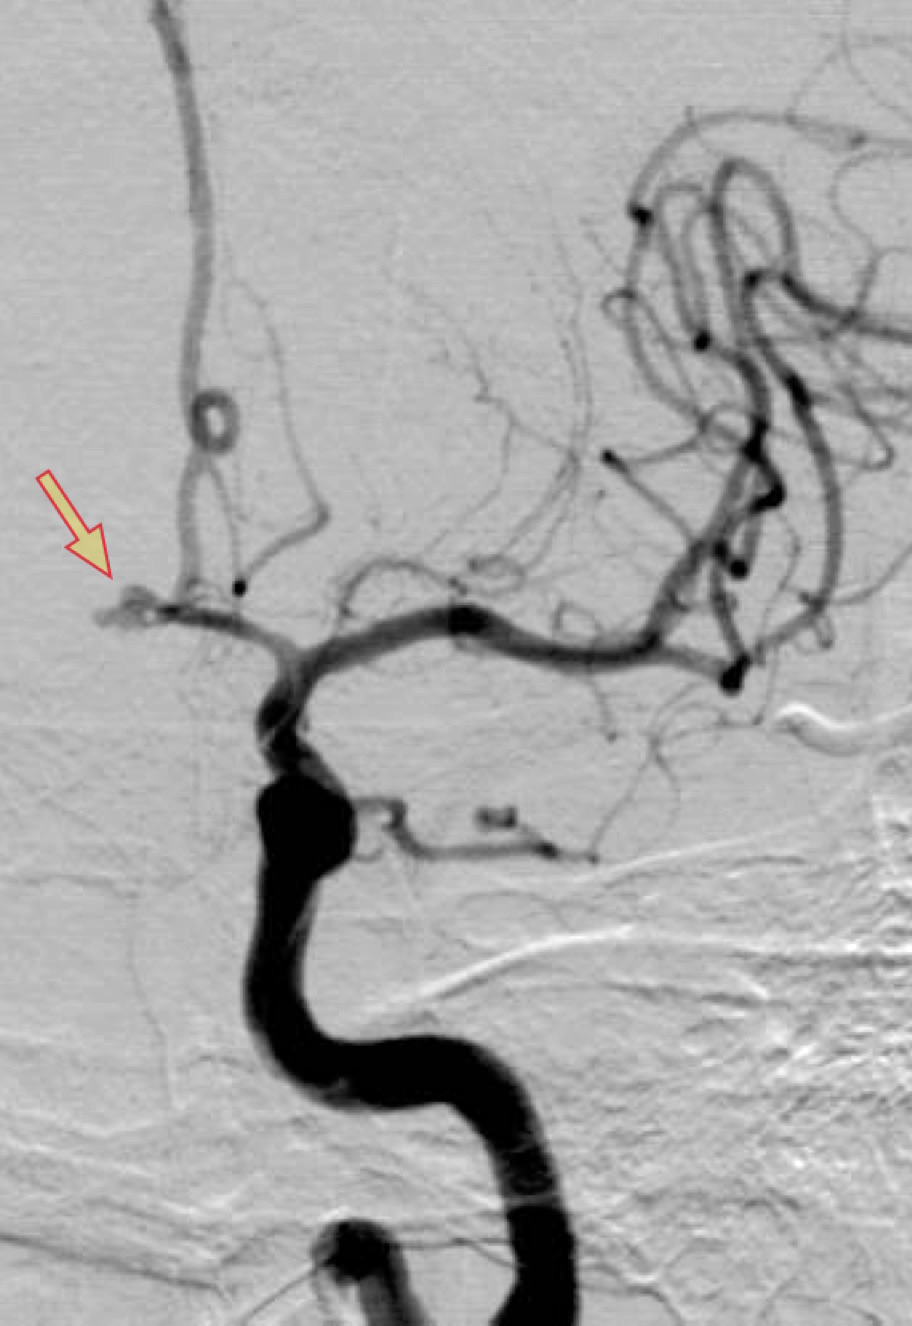

特に即効性があるのはバルーンによる治療(PTA)です。以下に、私の経験した症例を提示いたします。

遅発性脳血管攣縮に対するPTA治療

<治療前>矢印の部分が狭窄部

<治療後>矢印の部分が治療後に拡張した部分